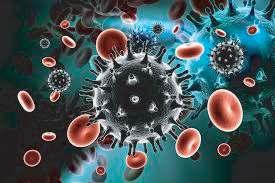

Infección por VIH/SIDA.- Es una enfermedad infecciosa que afecta al sistema inmunológico humano, encargado de proteger el organismo de las agresiones externas. Al agente causante del SIDA se le denomina Virus de la Inmunodeficiencia Humana (VIH).

El VIH se transmite principalmente a través de contacto sexual sin protección, compartir agujas contaminadas, transfusiones de sangre no seguras o de madre a hijo durante el embarazo, el parto o la lactancia materna.

Aunque no existe una cura para el VIH, los avances médicos han llevado al desarrollo de terapias antirretrovirales que pueden ayudar a controlar la infección y permitir que las personas infectadas vivan vidas más largas y saludables.

La prevención sigue siendo fundamental en la lucha contra el VIH/SIDA, incluyendo el uso de condones durante las relaciones sexuales, la realización de pruebas de detección regulares, el acceso a la educación sobre salud sexual y reproductiva.

El acceso a servicios médicos y tratamientos adecuados. La reducción del estigma y la discriminación hacia las personas que viven con VIH también es crucial para garantizar que reciban el apoyo y la atención que necesitan.